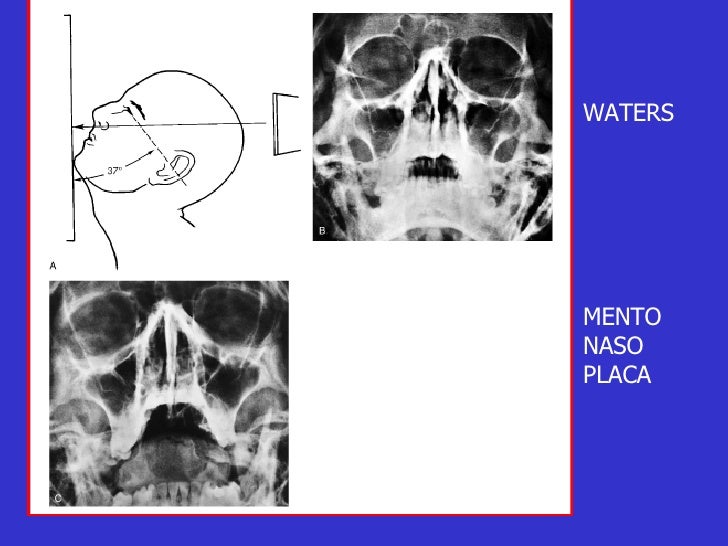

Download scientific diagram | Proyección de Waters: aumento de densidad de partes blandas de los senos maxilares (estrella) y presencia de masa en la faringe (flecha). from publication: Pólipo.. Citation, DOI, disclosures and article data. The Caldwell view is a caudally angled radiograph, with its posteroanterior projection allowing for minimal radiation to the orbits. This view may be used in imaging of the skull or facial bones depending on the clinical indications.

Dx por imagen Craneo Columna RADIOGRAFIA DE CRANEO Proyección de Waters, esta proyección nos

Waters de Cráneo Orthodiagnóstico

ESTUDIO RX 4 Proyeccion de Waters YouTube

Incidencias de CADWELL y WATERS NeuroMedicine uDocz

Descarga RX – Posiciones Radiológicas: https://play.google.com/store/apps/details?id=com.Tarter.RXPosicionesRadiolgicas&pcampaignid=web_sharehttps://apps.app.. Study with Quizlet and memorize flashcards containing terms like Proyección de Caldwell también llamada., Proyección de Waters también llamada., ¿Qué estructuras se aprecian mejor con la proyección de Caldwell? and more.